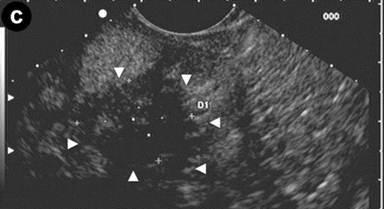

Patient#3: Focal form of autoimmune pancreatitis.

A 43-year-old man referred to us for abdominal pain and weight loss. IgG4 levels were elevated (298 mg/dL). Coronal scans with contrast enhanced CT (Image 3ab) showed the pancreatic head was enlarged with hypodense areas (2.7 cm, arrow) without vascular involvement of the mesenteric vessels. The pancreatic duct was dilated in both the body and the tail regions (arrowhead); the biliary tree was normal. The CT scan findings suggested pancreatic cancer. EUS and EUS-FNB were requested. Linear scanning (Image 3c) showed an enlarged pancreatic head with a focal hypoechoic mass (22 mm measured with calipers) with irregular margins (arrowheads). Upstream dilatation of the main pancreatic duct (8 mm, measured with calipers) in the body-tail regions was associated with the echopoor focal lesion (arrowheads); the lesion had close contact with the superior mesenteric vein (Image 3d). On EUS Doppler study (Image 3e), the echopoor lesion of the pancreatic head (arrowheads) appeared hypovascular; the superior mesenteric artery (arrow) and vein were patent.